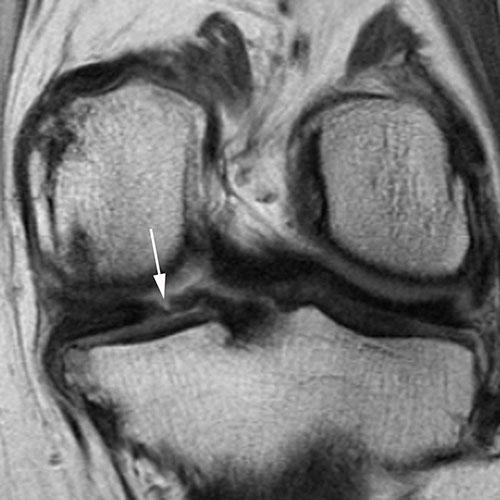

Sagittal intermediate-weighted fat-saturated image shows a typical horizontal-oblique meniscal tear of the posterior horn reaching the undersurface of the meniscus (arrows).